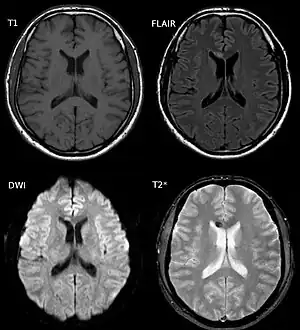

a-f)Diffuse axonal injury on MRI

Diffuse axonal injury after a motorcycle accident. MRI after 3 days: on T1-weighted images the injury is barely visible. On the FLAIR, DWI and T2*-weighted images a small bleed is identifiable.